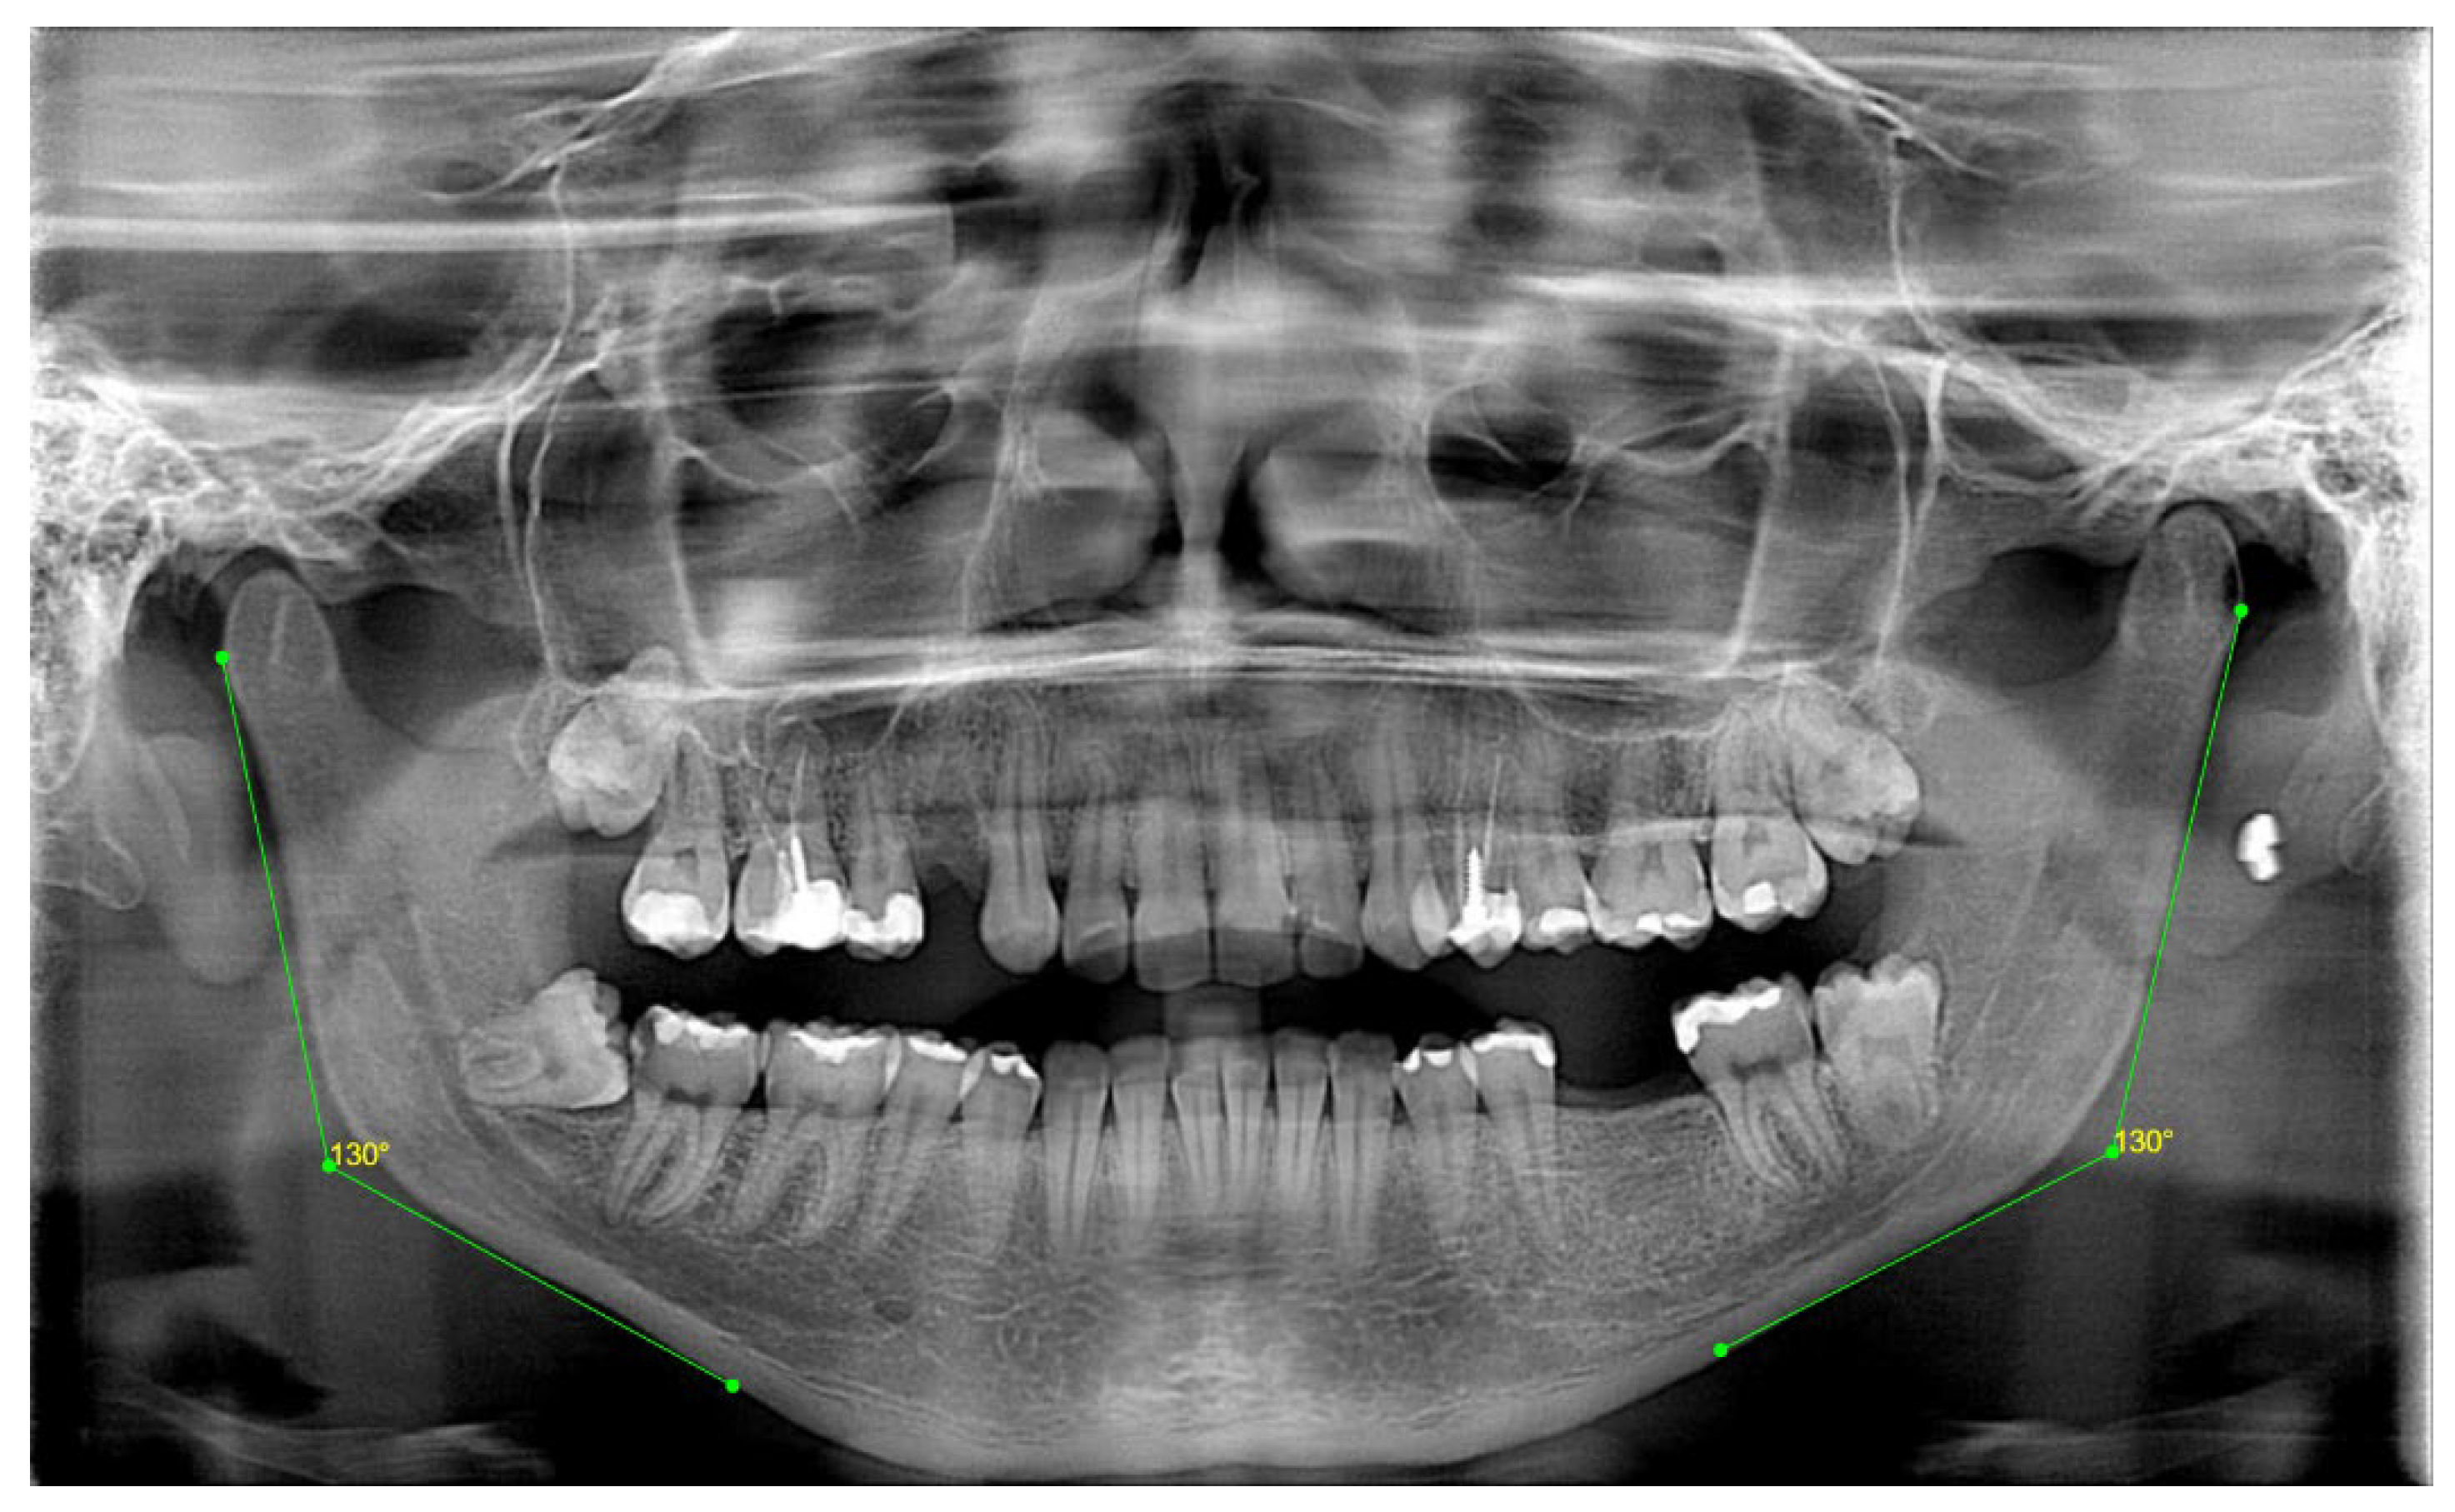

| 3 | GONIAL ANGLE (°) | At lateral cephalograms, it was determined at the junction of the mandibular and ramus planes. A line tangent to the lower border of the mandible and another line tangent to the distal border of the ascending ramus and the condyle on either side were drawn in order to measure the gonial angle in the panoramic radiographs [20]. The mandibular plane and the ramus plane’s built point of junction. |